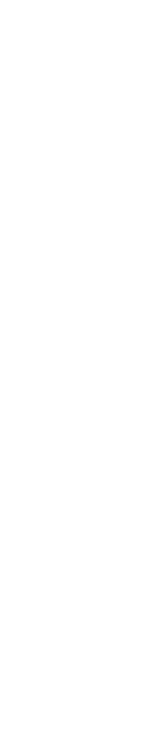

Les pleurésies sont fréquentes et sont des lésions qui touchent la région dorso-caudale du poumon, principalement associées aux formes subaiguës ou chroniques de la pleuropneumonie porcine (APP). Elles se manifestent sous forme de zones blanchâtres sur la plèvre viscérale des lobes diaphragmatiques, qui correspondent à des dépôts de fibrine.

Pleurésie crâniale

Pleurésie crâniale

Pleurésie crâniale